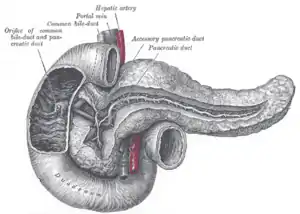

Diagram of the human duodenum with major parts labelled | |

Transverse section through the middle of the first lumbar vertebra, showing the relations of the pancreas The pancreatic duct

The pancreatic duct Region of pancreas